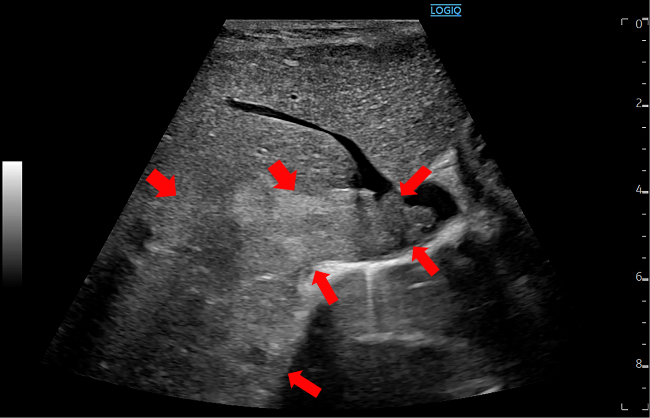

腹部造影CT検査で、肝右葉を占める塊状型肝細胞癌がみられ、右肝静脈から下大静脈に至る腫瘍浸潤ならびに門脈腫瘍栓が指摘された(図1)。腹部超音波検査ではBモードで下大静脈から右肝静脈にかけて進展する占拠性病変がみられた(図2)。上腸間膜動脈からの血管造影検査では門脈内に陰影欠損像が描出されたが、明らかなThreads and streaks signは指摘できなかった(図3)。